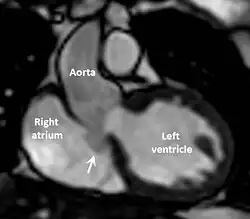

Cardiac MRI scan showing intact sinus of Valsalva aneurysm (arrowed) extending from non-coronary cusp to right atrium.

The first step in diagnosis is typically transthoracic echocardiography. However, if surgery is planned or if the standard echocardiogram lacks sufficient detail, then one or more additional studies are recommended. These studies include transesophageal echocardiography, 3D echocardiography, CT Angiography and aortic angiography.[4] Cardiac MRI may be another option.[2]